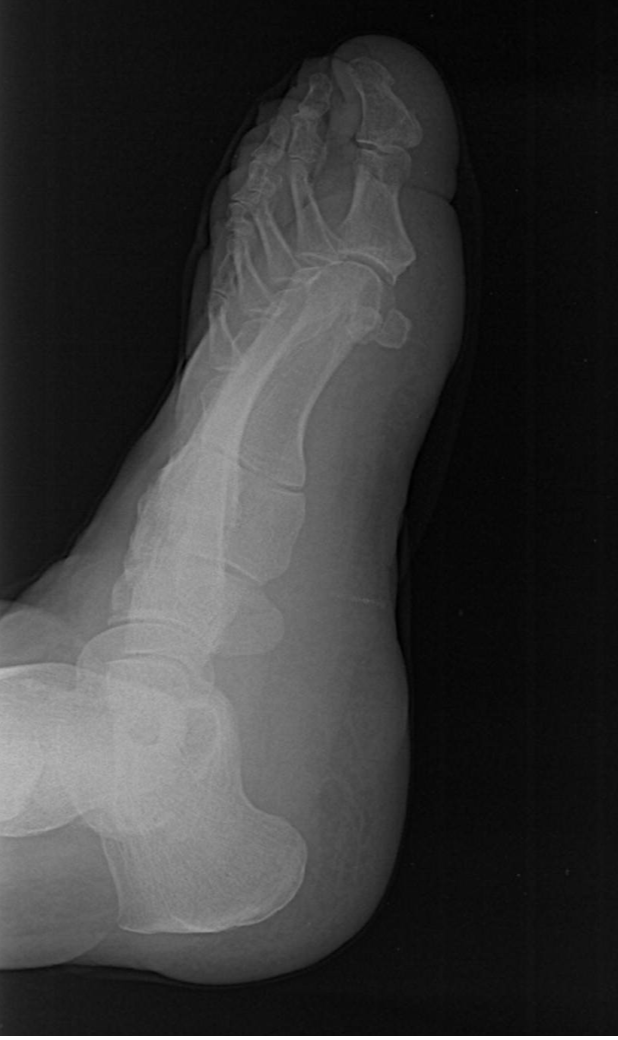

9

Q

What view is this?

A

Lateral Oblique